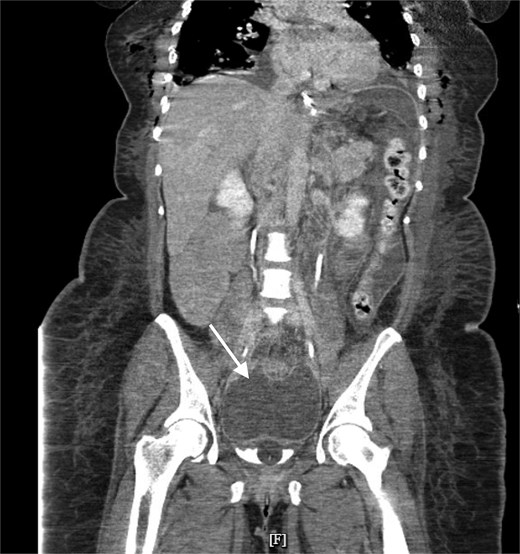

A 41 year old female presented to the emergency department with clinical presentation of peritonitis 4 days after a robot-assisted laparoscopic cholecystectomy, hiatal hernia repair, and gastric sleeve converted to Roux-en-Y gastric bypass. The patient underwent a diagnostic laparoscopy and was found to have a necrotic Roux limb in the setting of venous congestion. The Roux limb along with the necrotic congested mesentery was resected, and the Roux-en-Y gastric bypass was recreated. Postoperatively, the patient developed fevers and tachycardia despite receiving broad-spectrum antibiotics. Labwork showed leukocytosis to 16.1 with left shift to 81.5%. Computed tomography (CT) scan showed a saddle pulmonary embolism and pelvic fluid collection measuring 14.2 × 7.5 cm (Figs 1 and 2). The patient was started on therapeutic anticoagulation, and interventional radiology (IR) was consulted. No thrombectomy was indicated as there were no signs of right heart strain, however IR placed a 8.5 French drainage catheter in the abscess cavity. Wound cultures grew Enterococcus faecalis Group D and Proteus mirabilis.

Pelvic fluid collection prior to IR drainage measuring 15.4 × 10.6 cm, in the axial view.

Pelvic fluid collection prior to IR drainage measuring 15.4 × 10.6 cm, in the coronal view.